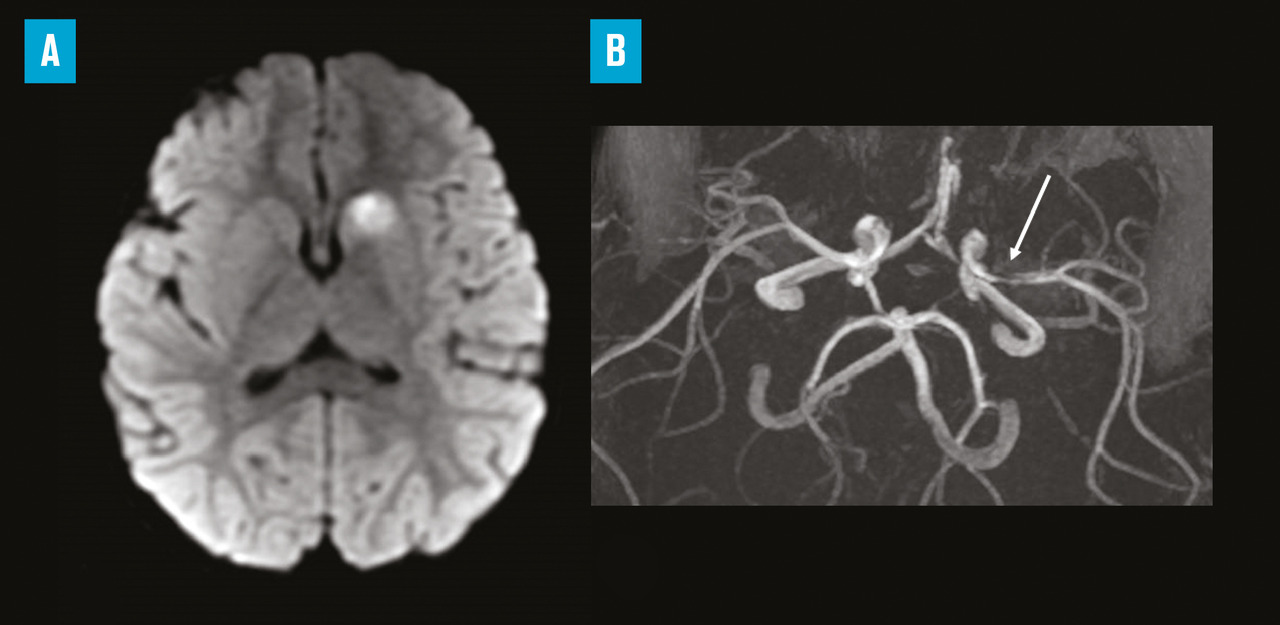

La simple évocation du diagnostic doit conduire à une prise en charge spécialisée immédiate, suivant une filière de soins pédiatrique (ou individualisant les enfants au sein d’une filière générale) identifiée préalablement, de type « alerte AVC ». La filière permet un accès rapide à l’imagerie diagnostique et à un avis spécialisé pour l’utilisation de thérapeutiques de recanalisation artérielle de la phase hyperaiguë. L’imagerie par résonance magnétique (IRM) est l’imagerie diagnostique de référence. En effet, un déficit neurologique focal aigu est secondaire à un AVC dans seulement 20 % des cas chez l’enfant. Outre le fait que la tomodensitométrie ne permet pas le diagnostic à la phase hyperaiguë de l’infarctus artériel cérébral, il n’identifie pas non plus les diagnostics différentiels les plus fréquents (migraine accompagnée, déficit postcritique…), nécessitant pourtant une prise en charge neuropédiatrique adaptée urgente.6 En France, l’établissement de filière de prise en charge des alertes AVC enfant est piloté par région, faisant intervenir les acteurs de l’urgence préhospitalière et hospitalière, neurologues vasculaires des unités neurovasculaires, pédiatres et neuropédiatres, radiologues, réanimateurs pédiatriques. Toute suspicion d’AVC chez l’enfant doit faire l’objet d’un appel au 15 – comme recommandé chez l’adulte – afin de permettre une régulation préhospitalière pour une entrée rapide dans la filière de soins dédiée. Ainsi, le patient a un accès direct en IRM dans un centre préparé à l’accueil des enfants suspects d’AVC, un avis spécialisé, la possibilité d’une hospitalisation en unité de surveillance continue pour la prise en charge initiale.7

Parmi les artériopathies intracrâniennes, l’artériopathie cérébrale focale de l’enfant est la plus fréquente. Il s’agit d’une entité assez spécifique à la petite enfance, caractérisée par une sténose d’allure inflammatoire – souvent post-infectieuse – intéressant typiquement le segment proximal de l’artère cérébrale moyenne, évoluant durant quelques semaines et sans récidive ultérieure. Les infections virales, notamment respiratoires hautes, et la varicelle sont les causes les plus fréquentes de ces artériopathies focales transitoires. La prévention des récidives précoces par aspirine est efficace, et le traitement peut ensuite être arrêté 18 à 24 mois après l’AVC, lorsque tous les critères diagnostiques (notamment l’absence d’évolutivité de l’atteinte artérielle) ont été réunis.